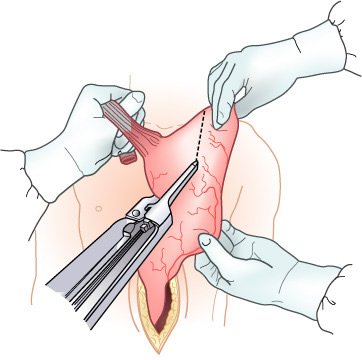

Após completar a esofagectomia transiatal para tumor localizado no terço distai, é confeccionado o tubo gástrico com o emprego de grampeamento mecânico da grande curvatura, ressecando o máximo de estômago possível distai ao tumor macroscópico. O restante do estômago é, então, posicionado no mediastino posterior no leito esofágico original e anastomosado ao esôfago cervical O grampeador cirúrgico é utilizado para a confecção do tubo gástrico a partir da grande curvatura gástrica com preservação de todo o comprimento.

O grampeador é fechado, com aproximação das pás; mas, antes de dispará-lo, realizam-se dois pontos de suspensão em cada lado, entre o estômago anterior e o esôfago adjacente. B, Quando a lâmina do grampeador é avançada, a "parede comum" entre o esôfago e o estômago é seccionada, criando-se uma anastomose ipsilateral de 3 cm de extensão. Então, a sutura dos ângulos é feita em cada lado da gastrotomia. C, A gastroto-mia e o esôfago aberto remanescente são aproximados em duas camadas

O local de secção cranial é, então, escolhido aproximadamente a 10 cm acima da porção mais superior do tumor. A margem gástrica é de, pelo menos, 5 cm da porção mais inferior do tumor. O restante do estômago é levado para o mediastino posterior e a anastomose realizada (término-terminal ou término-lateral) utilizando tanto plano manual único ou duplo quanto grampeadores.

A esofagectomia torácica total é semelhante, porém inclui a remoção completa de todo o esôfago para maximizar a ressecção. Este procedimento tem início com a laparotomia, para mobilização do conduto escolhido. A toracotomia direita é realizada e o esôfago ressecado de 5 cm da margem gástrica a partir da cárdia até 2 ou 3 cm do EES. O conduto, tanto no estômago quanto no cólon, é posicionado retroesternal ou no leito original do esôfago, e a anastomose cervical é realizada.

Esofagectomia com interposição de segmento antiperistáltico do cólon. A, Incisões usadas para realizar a esofagectomia, esofagostomia cervical, piloromiotomia e gastrostomia. B, Extensão da ressecção esofágica (área sombreada). C, Preparo do segmento de cólon esquerdo (área sombreada) para interposição baseada na artéria cólica média (perceba os locais de interrupção da vascularização, que preservam a integridade da arcada vascular). D, Operação completa.